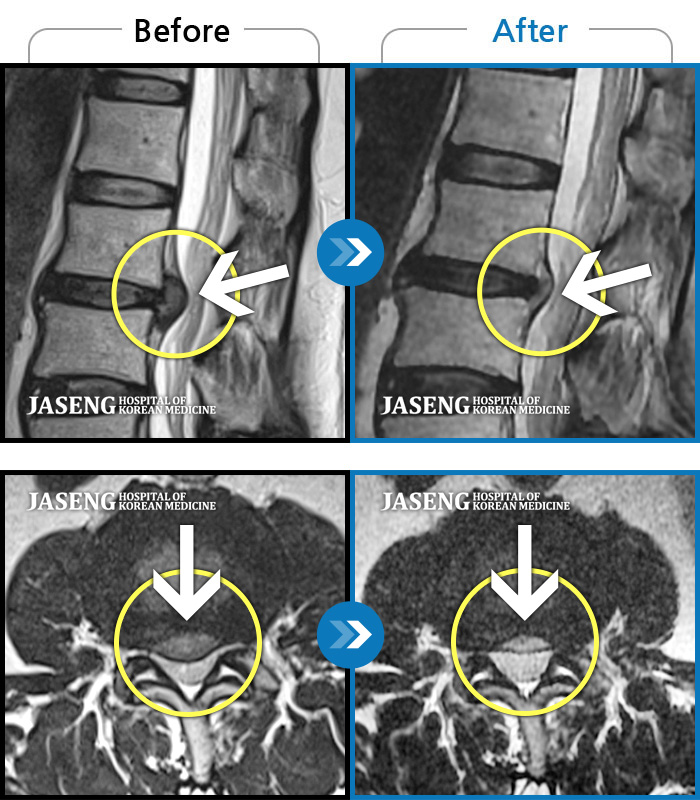

24년 3월 디스크파열 진단받고 극심한 통증으로 입원하여 김재영원장님께 치료받은 후 증상이 매우 호전되어 퇴원한 경험이 있습니다. 원장님께서 퇴원무렵 컨디션 관리를 엄청 당부하셨지만 근무하는 과정에서 발생하는 어쩔수 없는 과로와 극심한 스트레스는 서서이 좋아지던 저의 디스크 통증을 급기야 재발하게 만들었습니다. 7월말 다시 시작된 왼쪽 종아리와 발가락으로 퍼지는 심한 통증과 몸살로 더이상 근무를 계속할수 없어서 급하게 원장님을 뵙고 입원 치료하게 되었습니다. 김재영 원장님께 진료받고 극심했던 방사통이 진통제 없이 생활하기 까지 호전된 경험이 있고 원장님께서도 저의 상황을 어느정도 아시고 계셔서 이번에는 처음 디스크 터졌을때처럼 엄청 겁먹지 않고 원장님께 사소한 증상 하나하나 말씀드리면서 차분하게 치료받을 수 있었습니다. 제가 직장다니면서 힘든 마음으로 다시 입원하게 된 상황을 이해해 주시고 치료가 빠르게 될수 있도록 매일 소소한 증상 하나하나 신경쓰셔서 치료해주시고자 애써 주셔서 진심으로 감사했습니다. 심한 몸살이 디스크 통증과 함께 와서 소화도 안되고 기운도 없이 입원 첫주 무척 힘든 시간을 보냈습니다. 원장님께서는 소화가 잘 되게 침치료도 병행해 주시고, 소화제 종류도 다양하게 바꿔가며 저의 컨디션이 되돌아 올수 있게 처방을 해 주셨습니다. 무수히 많은 환자를 진료하시는 바쁘신 진료시간 중에서도 저의 증상을 매일 편하게 말씀 드릴수 있게 대해 주셔서 소소한 증상까지 말씀 드려 본의 아니게 원장님을 피곤하게 해드렸습니다. 입원 9일차 정도되니 그렇게 아팠던 종아리 통증은 거의 사라지고 소화기능도 조금씩 회복되고 있습니다. 통원치료때도, 입원치료때도 늘 한결같이 저의 증상을 귀담아 들어주시고 치료가 빠르게 될수 있도록 애써 주셔서 고맙습니다. 침 치료시에 어쩔수 없이 듣게 되는 다른 환자분들과 원장님과의 대화속에서도 치료받으시는 어버님 아버님들께서 원장님께 아픈 곳을 편히 말씀하시는것이 느껴졌습니다. 원장님께서도 일일이 다 성의껏 어르신들 말씀 귀담아 들어주시고 치료해 주시는것을 보니 원장님께서는 참으로 인품마저 다정하신 분 같았습니다. 거기에 아픈 통증도 꼭꼭 잡아주시니 원장님께 진료받는 많은 환자들이 원장님의 마음에 심적으로 안정을 받으시고 원장님의 전문적인 의료 도움을 크게 받는것 같습니다. 원장님께서 환자를 대해 주시는 따뜻함, 실력있는 의술 덕분에 제가 입원하는 기간 마음 편하게 치료 받을수 있었습니다. 통증이 자주 재발하면 완치되기가 힘드니 조심해야 된다는 원장님 조언 잘 새겨듣고 올 하반기에는 다시 입원하지 않도록 노력해 보겠습니다. ^^ 원장님께서도 남은 여름 건강 잘 챙기세요~~~ 고맙습니다. 김재영 원장님 ^^

저는 허리디스크 파열로 3월 1일부터 입원하여 3주째 해운대 자생 김재영 원장님께 입원진료를 받고 있습니다.

이번주에 퇴원할 예정이라 그동안 원장님께 진료 받고 조금씩 나이지고 있는 부분에 대해 진심으로 감사한 마음을 전하고 싶습니다.

김재영 원장님께서 혹시 모르니 그래도 MRI를 찍어보고 정확히 원인을 알고 치료를 하자고 권유하셔서 MRI를 찍게 되었습니다. 결과는 디스크 파열로 심각한 상황이었습니다.

저는 수술이 당장 시급한, risk가 상당히 있는 MRI 결과였지만 갑작스러운 결과에 수술을 바로 하기엔 너무 겁이 나서 일단 입원하여 원장님 치료를 받아보기로 마음먹고 바로 입원했습니다.

원장님께서 진료해 주시는 추나치료와 약침치료, 오후 병실 침치료, 물리치료 등을 받고 처방해 주시는 자생 한약을 꾸준히 복용했습니다. 야간에 더 심해지는 방사통으로 여러날 새벽을 야간 진료 선생님들 도움 받아가며 힘들게 하루하루를 버티고 있었습니다. 너무 힘들때는 참지 말고 야간 진료 선생님들 도움을 받고 푹 잠자는것이 치료에 더 도움이 될것이라는 말씀도 해주셔서 무조건 참는게 올바른 치료는 아니라는 점도 원장님께 배우게 되었습니다.

지옥같은 1주일이 지나고 아주 조금씩 방사통이 약해지기 시작했고 지금 입원 3주차에 접어들어서는 그렇게 심했던 방사통은 낮에 근무가 가능할 정도로 호전되었습니다.